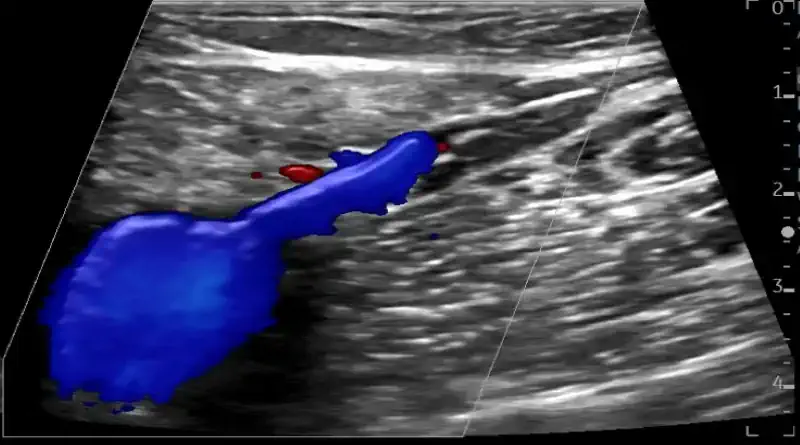

If you suspect a clot in a superficial vein, the next step is to get an ultrasound. There are two reasons for this. First, because the ultrasound will prove the diagnosis. But second, ultrasound will also show the clot extent. It is important to understand if the clot is extensive or if it is localized. It is also important to know if the clot is close to the deep veins, or if it is only in the superficial veins.